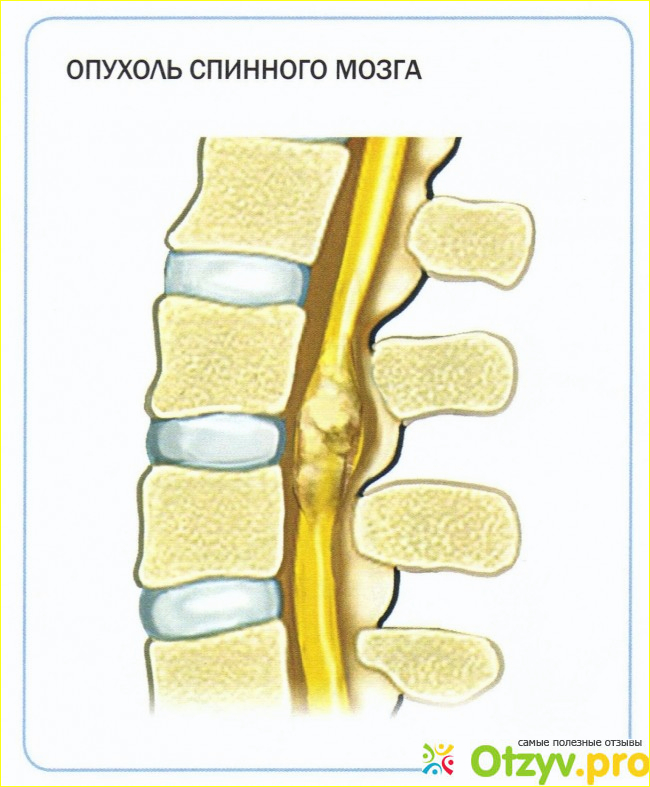

Отек спинного мозга что это

Отек спинного мозга что это 111 фото